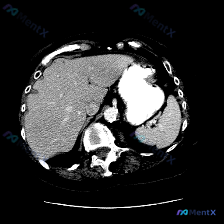

整理了一个很有意思的读片资料,先看一下基本情况: 影像资料概况 - 扫描部位:上腹部横断面CT(软组织窗) - 图像质量:清晰,对比度适中,无明显运动伪影 - 显示结构:肝脏、胃、脾脏、腹主动脉、椎体及周围软组织 主要影像描述(按器官整理) - 肝脏:形态轮廓尚平滑,实质密度均匀,未见明显局限性肿块...

看到一个很有意思的影像分析案例,整理了一下思路和大家分享: --- 【先看影像分析的客观结果】 这是一幅腹部增强CT横断面图像(腹主动脉内见高密度对比剂充盈,提示动脉期或血管期)。 影像所见: - 脾脏:形态大小正常,无肿大;脾实质密度均匀,未见明确占位、梗死灶或局灶性强化异常。 - 其他结构:双侧...

整理了一份挺有意思的影像分析资料,和大家聊聊思路。 病例/影像背景 临床预设存在“脾脏病变”,提供了一张腹部CT横断面(软组织窗)图像。 影像核心观察 我先把图像里的关键信息理一理: 1. 脾脏本身:左侧脾脏形态、大小、实质密度都大致正常,没有看到局灶性的低密度或高密度影,边缘也光滑 2. 其他腹部...